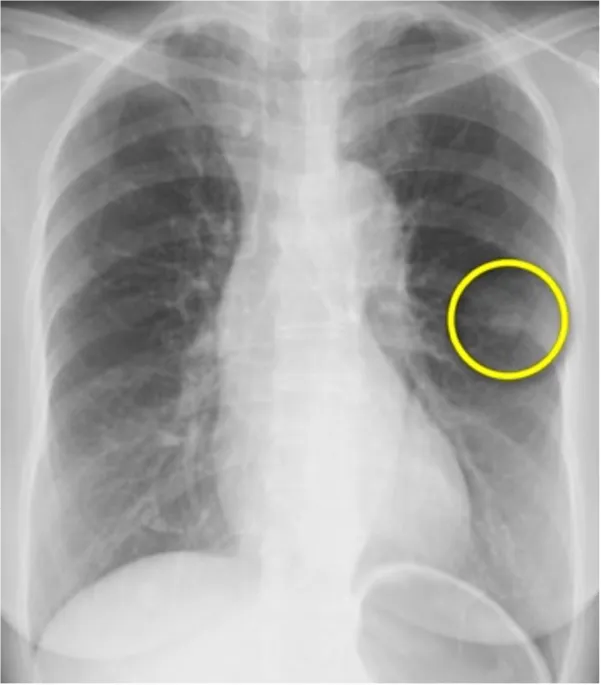

① 肺癌

我が国において、「がん」によって亡くなった人は1981年に脳卒中を抜いて第1位となり、現在、およそ3人に1人は「がん」によって亡くなっています。その中でも肺癌の増加は特に著しく、男性は1993年に胃癌を抜いて第1位に、女性においても大腸癌とともに増加して胃癌を抜いて第2位に、全体においても1998年に胃癌を抜いて第1位となりました。

肺癌の治療については、迅速かつ的確な診断を基に、その肺癌の種類(組織型)や進行度によって適切な治療が必要となります。肺癌の治療には「手術」、「抗癌剤治療」、「放射線療法」と大きく分けて3種類あり、肺癌の種類や進行度によっては、これらの治療を組み合わせた「集学的治療」が必要となります。